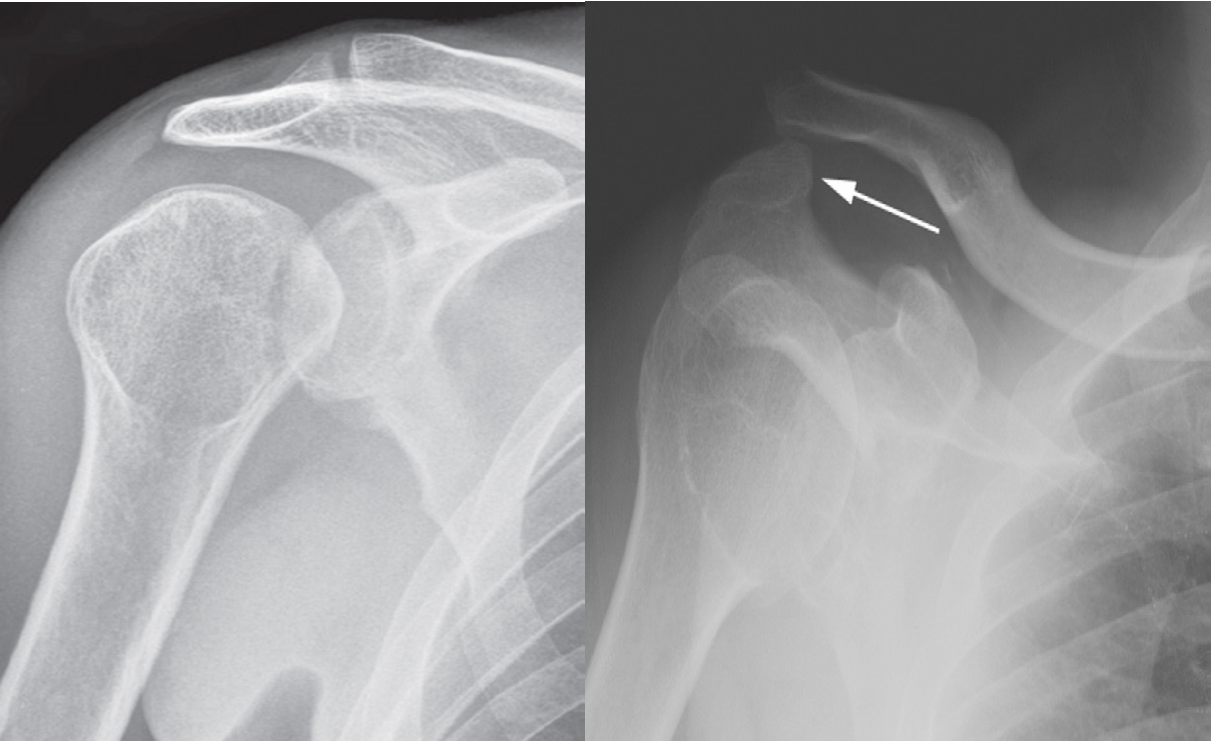

A. Posterior dislocation of the shoulder is often a consequence of an electric shock or epileptic seizure. z Note the internal rotation of the humerus and lack of congruity of the humeral head with the glenoid. Note the ‘lightbulbappearance of the humeral head.

four e’s elderly, electrical, epilepsy, ethanol

z B. Acromioclavicular dislocation; Capsular and ligamentous tears of the acromioclavicular ligaments allow the outer end of the clavicle to be displaced upward relative to the medial aspect of the acromion process (arrow).